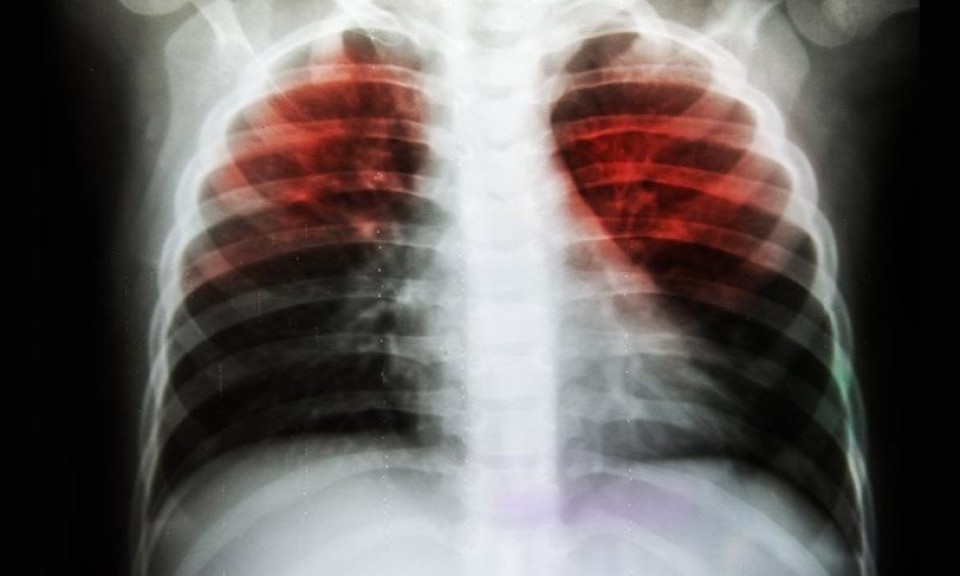

Türk Toraks Derneği Merkez Yönetim Kurulu Üyesi Dr. Fatih Tekin, tüberküloz (verem) hastalığının en çok öldüren bulaşıcı hastalık olduğunu belirterek, ülkemizdeki sağlık çalışanlarının verem konusundaki başarısına dikkat çekti.

Tüberküloz dünyada en önemli 10 ölüm nedeninden biri. Türk Toraks Derneği Merkez Yönetim Kurulu Üyesi Dr. Fatih Tekin, "78'inci Verem Eğitim ve Farkındalık Haftası"na istinaden açıklamalar yaptı ve şunları söyledi: "Tüberküloz en çok öldüren bulaşıcı hastalıktır. Dünyada en önemli 10 ölüm nedeninden biridir. Ancak son 3 yıldır ülkemizde tüberküloz raporları yayınlanmamaktadır.”

Tüberküloz hastalığı konusunda ve verem savaşı programı konusunda toplumun eğitiminin amacıyla öncü bir uygulama olduğunu belirten Dr. Tekin, dünya genelinde tüberküloz verilerine dikkat çekti; "Dünyada tüberküloz hastalığı, 2023 yılında artışını sürdürmüştür. Toplam 10.8 milyon tüberkülozlu hastanın yüzde 76’sı yani 8.2 milyonu kayıtlıdır. 2020 yılında başlayan Covid-19 salgını sırasında verem hastalarının yüzde 57’si kayıtlı iken, salgının etkisi geçince kayıtlı hasta oranı artmıştır. Covid-19’un yol açtığı ölümler 2020 ve 2021 yıllarında tüberkülozdan fazla olmuştur. Covid-19 salgınının etkisi azalınca 2022 ve 2023’te tüberküloz ölümleri bulaşıcı hastalık ölümlerinde yine birinci sıraya yükselmiştir. Tüberküloz, en çok öldüren bulaşıcı hastalıktır. Dünyada en önemli 10 ölüm nedeninden biridir. Afrika ve Asya’da ciddi, ekonomik olarak yıkıcı, çok sayıda ölüme yol açan bir hastalık olmayı sürdürmektedir. Hastalığın en çok etkilediği Hindistan, Endonezya gibi ülkelerin, sağlık alt yapılarının yetersizliği yanında ekonomik sorunları da büyüktür. Yoksulluk, yetersiz beslenme tüberküloz hastalığının oluşmasında en önemli nedenlerden biridir. Bu nedenlerle, uzun yıllar bu hastalığın acıları sürecektir.”